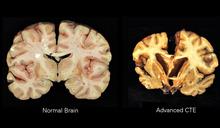

Presently, the only definitive way to diagnose chronic traumatic encephalopathy is by post-mortem autopsy, The diagnosis of CTE requires the accumulation of Tau proteins that cluster around the brain’s blood vessels. This disease progresses to involve more areas of the brain with evidence of degeneration of brain tissue.

Early on, the tau protein may be localized to a certain region of the brain. For example, the protein may accumulate around blood vessels in the brain’s cortex and the person may exhibit mild symptoms. As time goes on, the destructive protein spreads to other parts of the brain eliciting different and more severe symptoms.